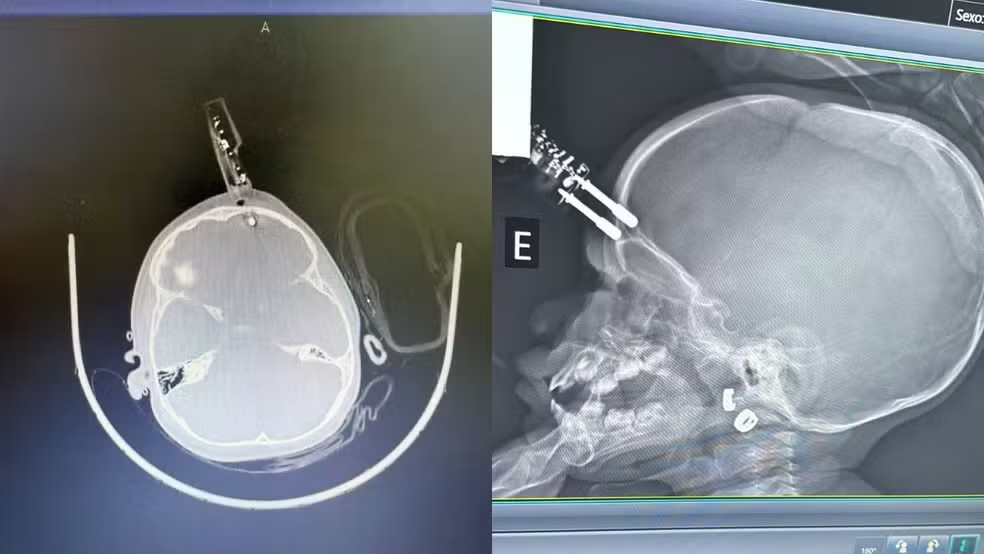

Menina fica com carregador cravado na cabeça em MG — Foto: Bruno Castro/Arquivo Pessoal

O caso aconteceu na última terça-feira (13). Segundo o neurocirurgião Bruno Castro, responsável pelo atendimento, a principal hipótese é que a criança estivesse segurando o carregador no momento da queda. O objeto perfurou o osso do crânio, próximo ao olho, e atingiu o tecido cerebral.

“A única possibilidade plausível é que ela estava com o carregador na mão e caiu junto com ele. Por azar, o objeto entrou na testa. Se tivesse atingido o olho, poderia ter causado perda da visão, o que felizmente não ocorreu”, explicou o médico.

Menina de um ano fica com carregador de celular cravado na testa após cair da cama em Divinópolis — Foto: Bruno Castro/Arquivo Pessoal

Diante da situação, a menina foi levada imediatamente ao bloco cirúrgico. O procedimento incluiu a retirada do objeto, limpeza da área, lavagem, fechamento e reconstrução da região afetada.

“A intervenção precisava ser imediata. Sem isso, o risco de hemorragia cerebral ou infecção grave seria muito alto”, destacou o neurocirurgião.